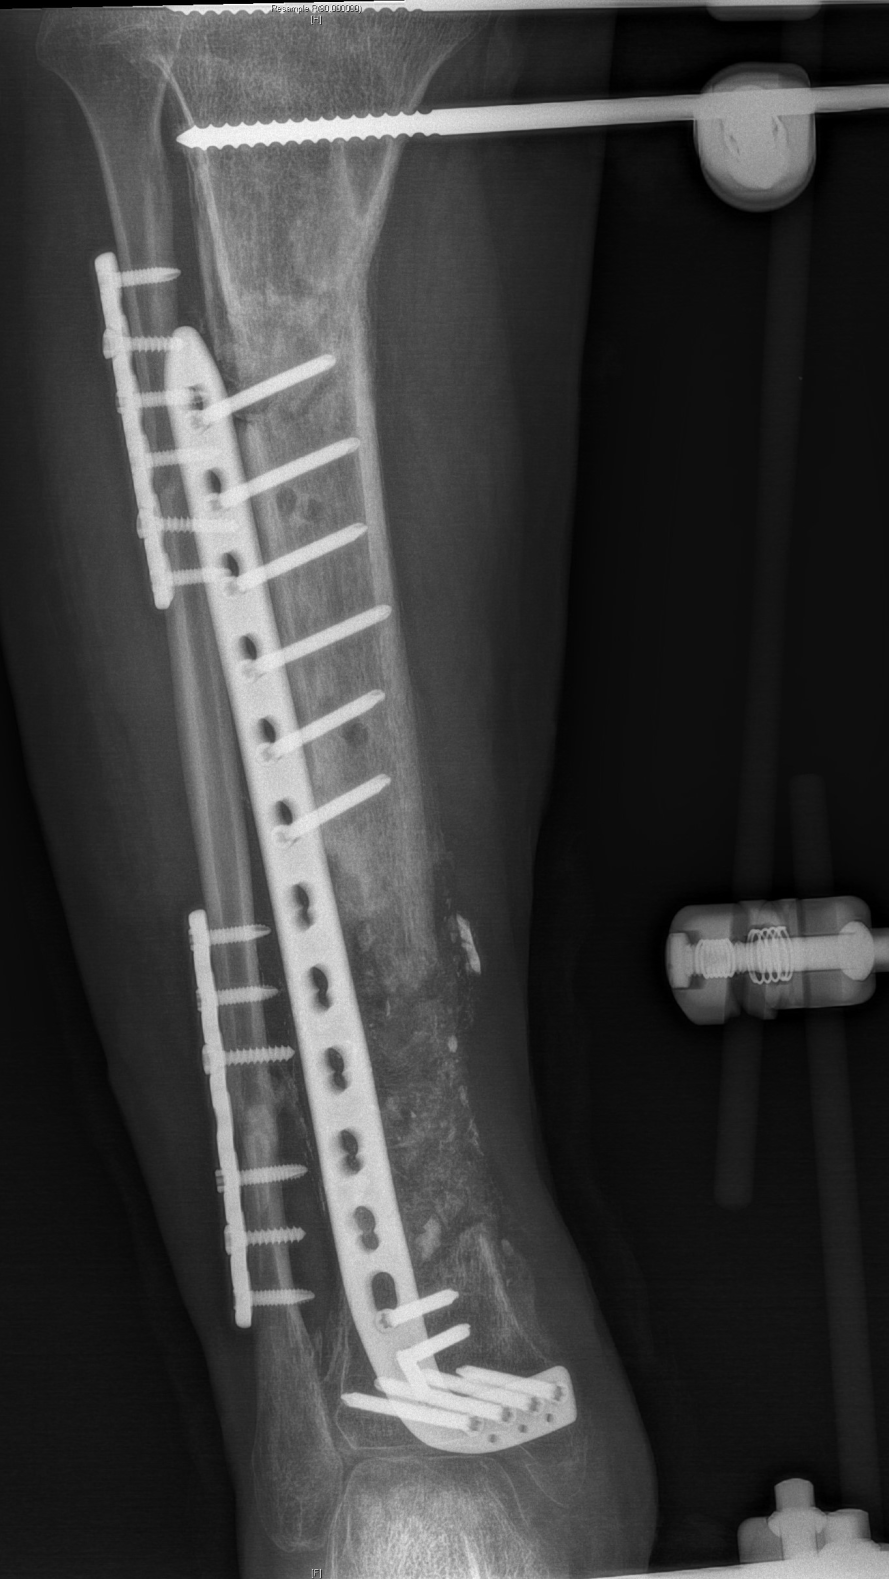

2、骨缺损重建

徐杨主任医师介绍,对于肢体毁损伤后期合并感染患者,保肢最大的难题是清创及骨与软组织重建,masquelet技术能够形成骨水泥诱导膜,不但能起到屏障作用,还含大量微血管,丰富血供,并能分泌各种促骨生长因子,具有成骨快、愈合率高的优点。尤其适合治疗长节段、严重感染性骨缺损病例。